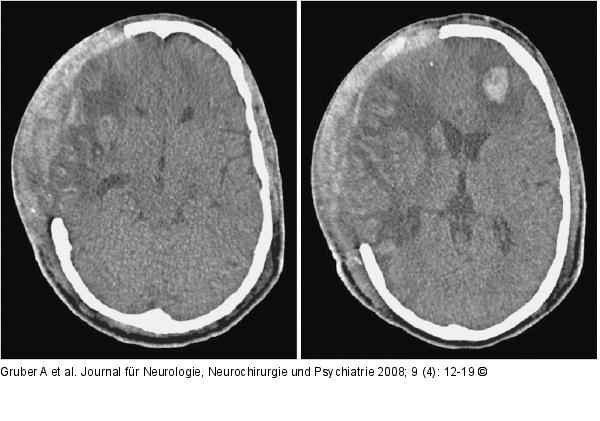

Abbildung 2: Therapie Eine begleitende thrombozytenfunktionshemmende medikamentöse Therapie erschwert wesentlich alle möglichen neurochirurgischen Maßnahmen (Entlastungskraniektomie, Hirndrucksondenimplantation) und geht mit einem erheblichen Blutungsrisiko einher. Extradural stellt im Besonderen die große Wundfläche mit diffuser Blutungsneigung an der Innenfläche des Hautlappens ein Problem dar. Subgaleale Hämatome nach osteoklastischer Trepanation wirken sich unmittelbar epidural raumfordernd aus. Saugdrainagen können wegen der bestehenden Duraeröffnung nicht eingesetzt werden. Der Temporalmuskel ist in vielen Fällen diffus blutig imbibiert und raumfordernd geschwollen. Insgesamt kann dadurch der dekompressive Effekt der Operation reduziert werden (a). Intradural ist im Speziellen die Hirnpunktion zur Implantation von Parenchymsonden zur Hirndruckmessung problematisch und kann in seltenen Fällen zu Parenchymblutungen führen (b). |